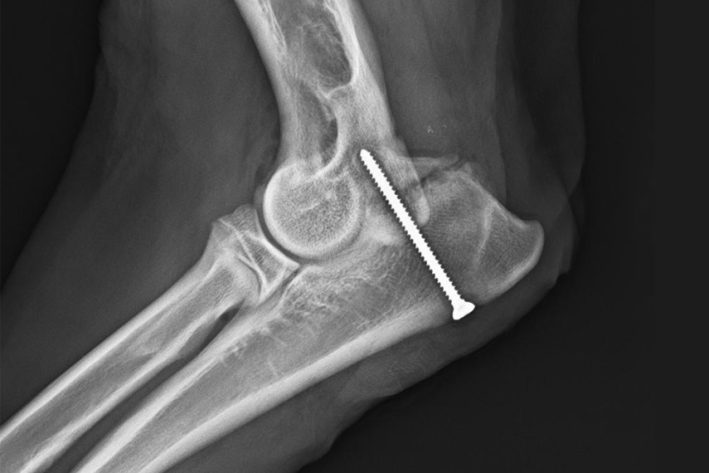

Isolierter Proc. Anconeus

Isolierter Pro. Anconeus vor dem Anschrauben

Proc. Anconeus Mit Schraube

Isolierter Proc. Anconeus nach dem Anschrauben